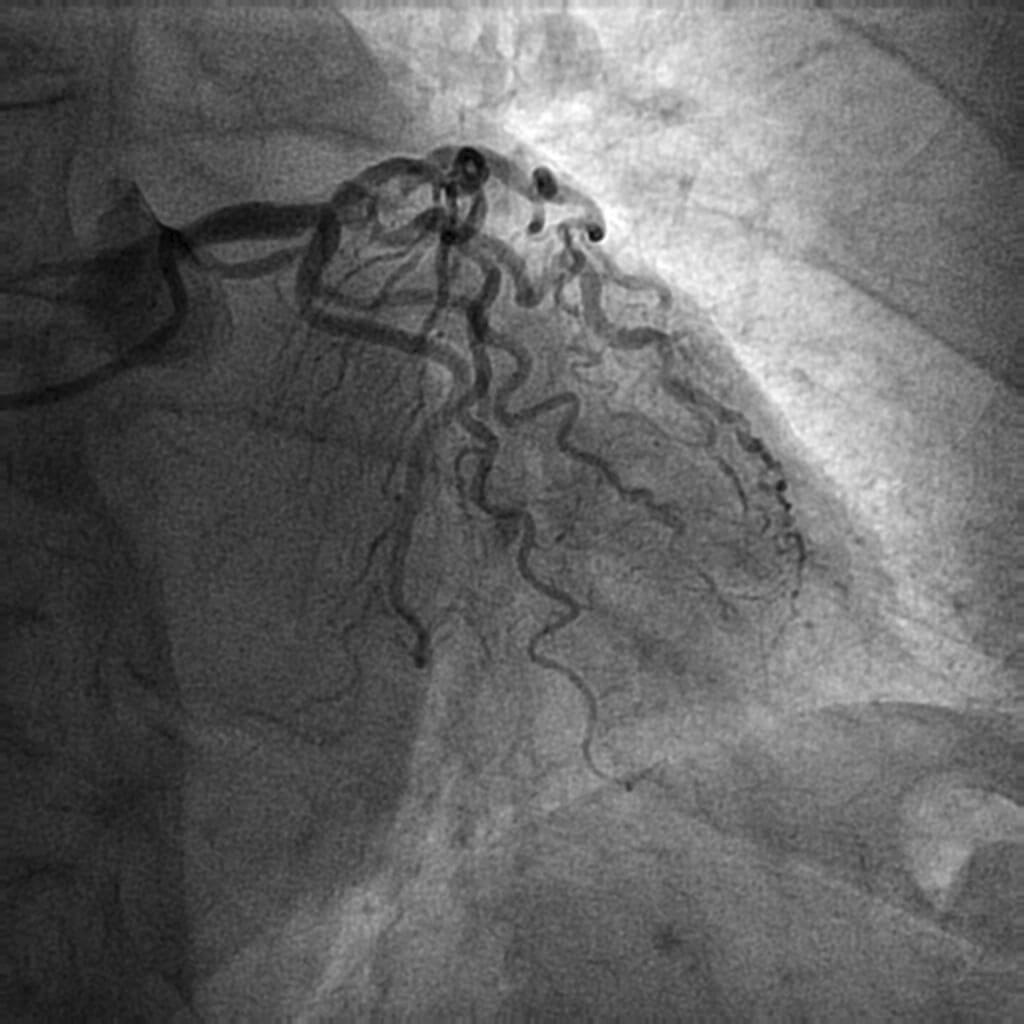

Se completó el estudio mediante coronariografía, en la que se observó enfermedad arterial coronaria del tronco común y de 2 vasos: tronco común largo y calcificado con lesión distal al límite de la significación que afectaba la bifurcación con la descendente anterior, 2 ramas intermedias y la circunfleja; la descendente anterior con lesión grave y calcificada ostial, primera y segunda ramas intermedias con lesiones significativas y calcificadas ostiales, y la circunfleja con lesión moderada ostial (figura 1, figura 2 y vídeo 1 del material adicional) con vaso distal de fino calibre y escaso recorrido. El aortograma mostró una válvula aórtica trivalva y calcificada, con apertura de los velos limitada e insuficiencia aórtica ligera; raíz aórtica y aorta ascendente no dilatadas y sin ateromatosis significativa (figura 3 y vídeo 2 del material adicional). La arteriografía de miembros inferiores mostró un eje ilíaco-femoral no calcificado ni tortuoso, con un diámetro mínimo de 7,3 mm en la arteria femoral común derecha y un diámetro mínimo de 7,7 mm en la arteria femoral común izquierda. Se calculó un riesgo a corto plazo de la Society of Thoracic Surgeons del 10,79%.

Figura 2. Angiografía coronaria en proyección oblicua anterior derecha caudal.